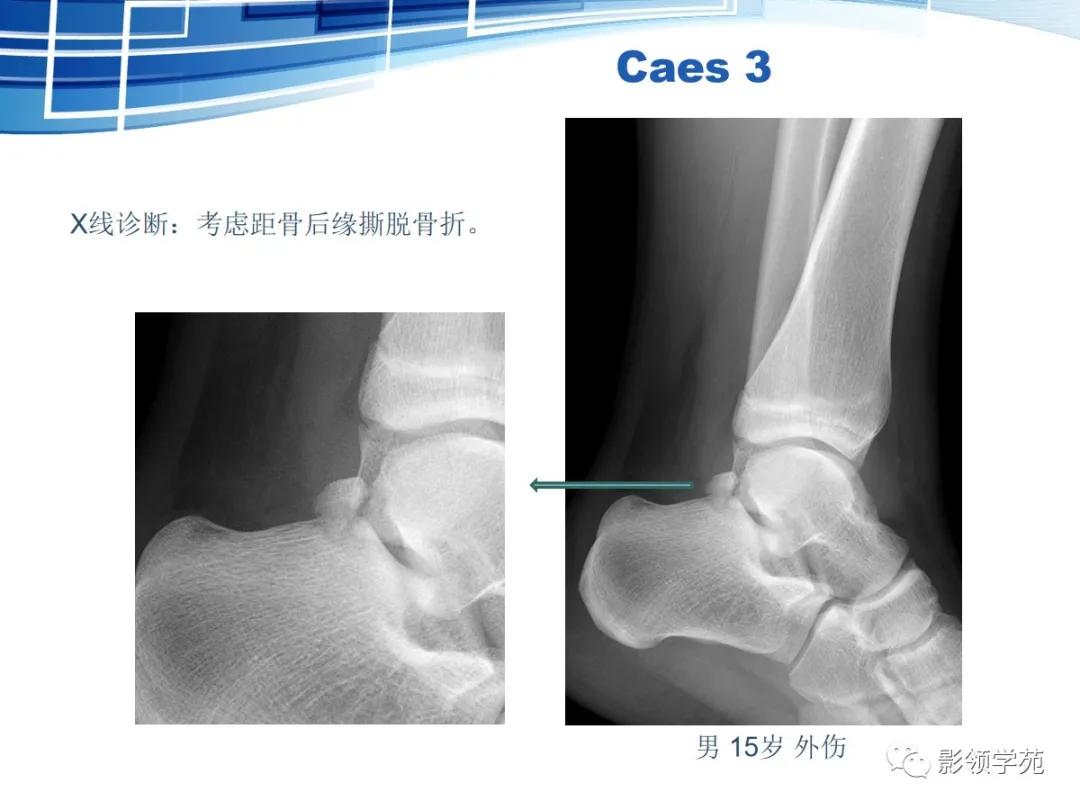

三角骨

-

三角骨是常见的变异,也被误称为距骨副骨。呈三角形, 与距骨后缘相切,三角骨与距骨后突外侧结节腓侧隐窝相对应。

三角骨可以成对存在,还可以与外侧结节融合,形成单一的突起,并可与距骨融合或形成关节。

三角骨与其它副骨一样,可妨碍足的运动,同时本身亦可受外界影响发生无菌性坏死。

正常变异:距骨三角骨